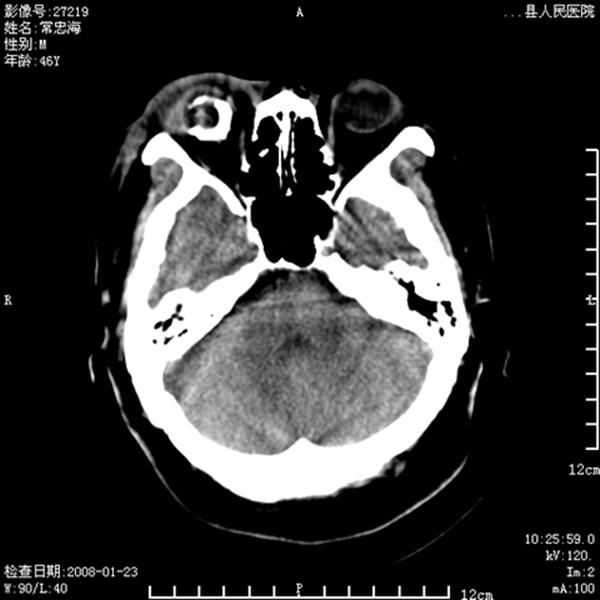

以下是引用江边学者在2008-4-19 22:26:00的发言:[br]1.胼胝体发育不良。[br]2.右侧眼球痨。[br]3.右侧颜面部软组织挫伤。